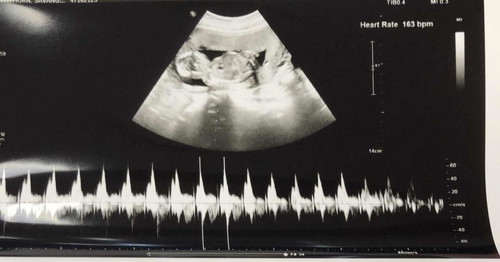

15W

แม่ๆมาแชร์รูปอัลตร้าซาวด์ตัวเล็กกันเถอะได้กี่Wกันบ้างแล้วคะบ้านนี้15W4Dayแล้วค่ะหมอบอกว่าน่าจะได้ผู้หญิงไม่เห็นกระจู๋เลย?